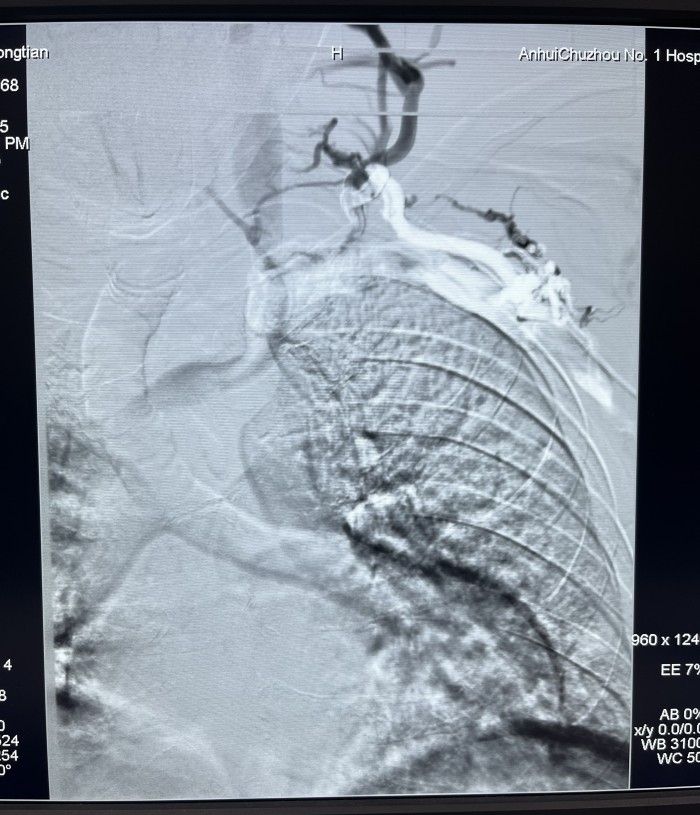

近日,我院介入血管科成功开展一例左头臂静脉重度狭窄球囊成形手术,挽救了患者的左侧桡动脉-头静脉人工

患者赵某,因两侧多囊肾致肾功能衰竭在我院行血液透析三年半。近一年来患者出现血透后左上肢肿胀并伴面颈部表浅静脉怒张,近三月透析时人工内漏内血流量下降。经我院介入血管科副主任芮兵门诊详细询问病史及查体后收治该患者入院,行左上肢CTV及左上肢静脉造影检查显示:左头臂静脉起始部重度狭窄。在芮兵主任医疗团队精心制定手术方案,除手术禁忌后,成功实施了经皮左头臂静脉球囊扩张成形术,术后患者左上肢肿胀明显消退,透析时血流量>200 ml/min,可以完成透析